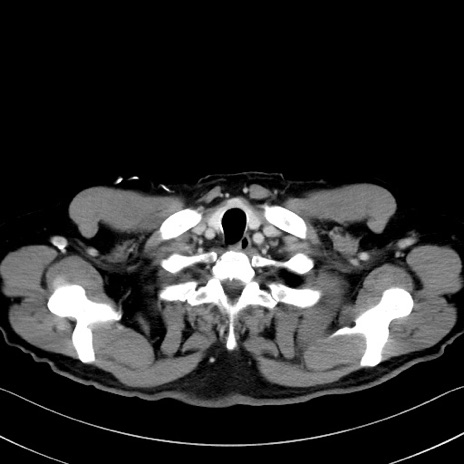

症例35(横断像)

【症例】70歳代 男性

【主訴】腹部膨満、嘔吐

【現病歴】昨日より腹部膨満感出現。本日増悪し、仙痛出現。嘔吐あり、受診。

【既往歴】糖尿病、胆摘後

【身体所見】BP 149/80mmHg、HR 74/min、BT 35.9℃、腹部:膨満、軟、圧痛なし。腸雑音減弱あり。上腹部正中切開瘢痕あり。

【データ】WBC 13500、CRP 1.72